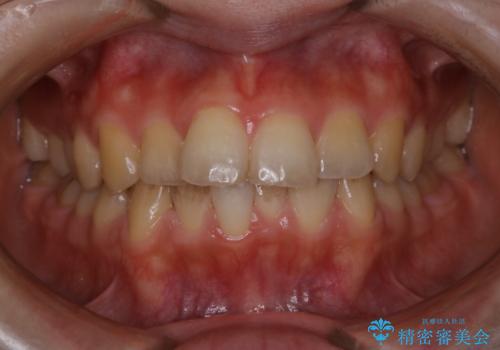

- 結婚式があるため、できる限りできれいにクリーニンングしてほしいとのことでした。PMTC60分コースを行いました。

プラークが放置されると、そこで歯周病菌が繁殖し始めます。よって歯肉に炎症が生じ、歯周病に引き金となります。

PMTC(保険外治療)は、毎日の歯磨きで落としきれない汚れや、コーヒ、紅茶・タバコのヤニなどの着色も除去します。目には見えない歯と歯の間・歯肉の境目などに残っているプラーク(歯垢)もしっかり取り除きます。PMTCでは専門的な機械や材料を使用して、徹底的に汚れを除去するため、虫歯・歯周病・口臭予防などにつながります。

またPMTCを行うことで、ご自身本来の歯の色になり自然な明るさになります。